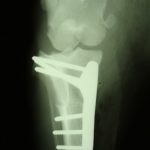

Osteosynthese: